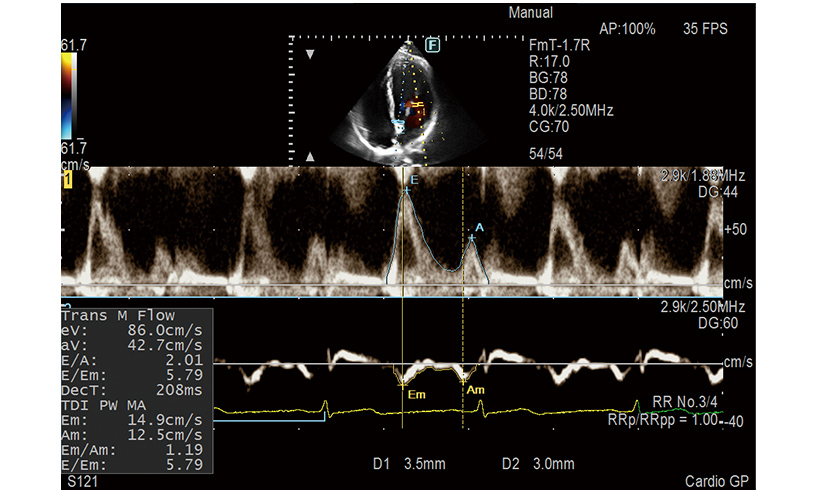

E/e', one of the key LV diastolic performance indices, is measured automatically in Dual Gate Doppler. Using this feature in combination with R-R Navigation, iDGD detects an appropriate heartbeat for measurement automatically.